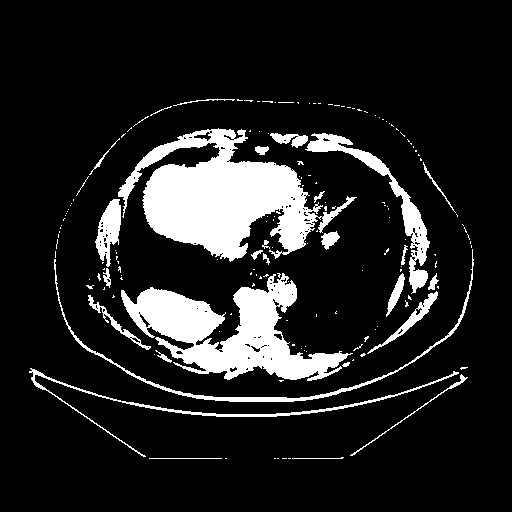

Image Grid

4Γ—3 grid: Rows show different image types (Original NATIVE, Reconstructed NATIVE, Original VENOUS, Generated VENOUS), Columns show windowing techniques (No Window, Lung Window, Mediastinum Window)

Generated VENOUS CT scan (A→B translation)

Full window (WL 1023.5, WW 4095 β†’ Low βˆ’1024, High +3071)

Actual HU range: [-1024.0, 3071.0]

Lung window (WL -600, WW 1500 β†’ Low βˆ’1350, High +150)

Actual HU range: [-1350.0, 150.0]

Mediastinum window (WL 40, WW 400 β†’ Low βˆ’160, High +240)

Actual HU range: [-160.0, 240.0]